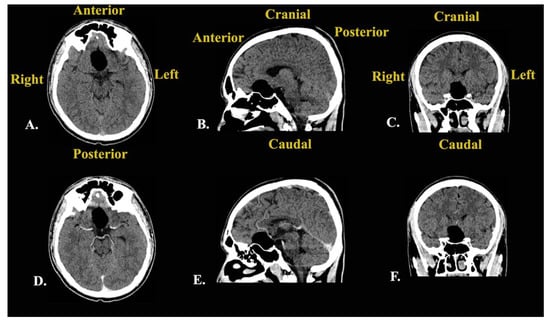

Following this investigation, a brain CT scan was performed to obtain more imagistic details (Figure 4).

Figure 4. Preoperative brain CT scan: (A) native axial sequence; (B) native sagittal sequence; (C) native coronal sequence; (D) contrast-enhanced axial sequence; (E) contrast-enhanced sagittal sequence; (F) contrast-enhanced coronal sequence.

The results depicted a tumoral mass, well delimited and localized at the median line in the suprasellar cistern and without a surrounding edema, without contrast enhancement, and with intrasellar prolabation. The lesion had a slightly inhomogeneous structure given the presence of areas with high densities (−27 UH, compared to −116 UH), corresponding to microcalcifications/hemorrhages/saponification of fats.